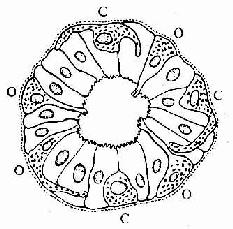

图12-24 消化管内分泌细胞模式图

示开放型(O)与封闭型(C)内分泌细胞

胃肠内分泌细胞大多单个地夹于其它上皮细胞之间,呈不甚规则的圆锥形。基底部附于基膜,并有基底侧突与邻近细胞相接触。胞质中含一些粗面内质网与高尔基复合体。细胞最显著的形态特点是底部胞质中含大量分泌颗粒,故又称基底颗粒细胞(basal granular cell)(图12-23)。分泌颗粒的大小、形状与电子密度依细胞类型而异。绝大部分细胞具有面向管腔的游离面,称开放型,游离面上有微绒毛伸出。此型细胞对管腔食物的刺激和pH变化等化学信息有较强的感受性,从而引起其内分泌活动的变化。少数细胞的顶部被相邻细胞覆盖而未露出腔面,称封闭型,主要受胃肠运动的机械刺激或其它激素的调节而改变其内分泌状态(图12-24)。分泌颗粒中含肽和(或)胺类激素,大多在细胞基底面释入固有层中的毛细血管,经血循环运送并作用于靶细胞;少数激素被释放后可直接作用于邻近细胞,以旁分泌方式调节靶细胞的生理功能。在HE染色切片上,胃肠内分泌细胞不易辩认;用铬或银盐浸染,少数种类的细胞可因其分泌颗粒具嗜铬性、嗜银性或亲银性而被显示。目前主要用免疫组织化学方法来显示这些细胞。